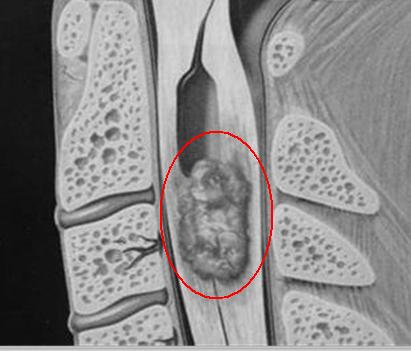

我们讲,椎管内肿瘤、寰枕畸形、先天性神经管畸形等疾病都可能导致患者出现颈、腰痛。但是由于诊断时排查不到位,等到经过相当长的时间治疗后,症状仍不见好转甚至严重到瘫痪、尿便*禁失**的程度时,才想到来神经外科就诊,而此时往往早已错过治疗的较佳时机,贻误终生。这样的例子在我们临床治疗工作中比比皆是。令我们临床医生及患者都倍感惋惜。